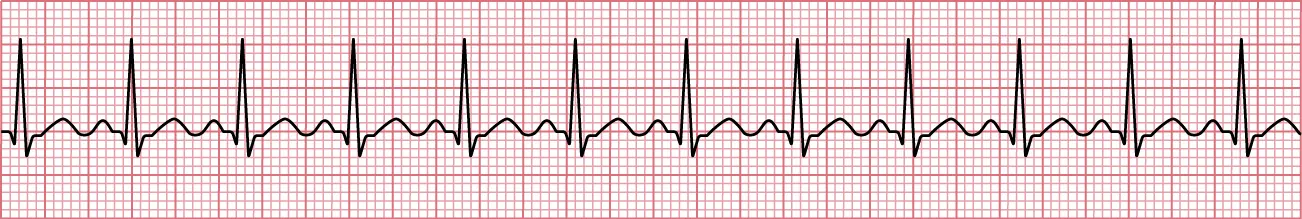

Ventricular disturbances are the most serious dysrhythmias and require prompt, emergent intervention. A ventricular tachycardia is when the ventricle beats rapidly at 150 to 200 bpm with wide QRS complexes (greater than 0.12 seconds) and no discernible PRs or P waves (Figure 12.16). A ventricular fibrillation is slightly faster than ventricular tachycardia with rates over 200 bpm (Figure 12.17). A classic finding in ventricular fibrillation is a chaotic baseline with no discernible QRS, PRs, or P waves. Patients with ventricular tachycardia may be able to report subjective feelings of fluttering, fatigue, and near syncope. The patient will be diaphoretic and have weak pulses. In severe cases, they can lose perfusion and have syncope. Ventricular fibrillation is considered a cardiac arrest as patients will lose consciousness and require advanced cardiac life support. Causation of these dysrhythmias can be from myocardial infarction, heart failure, electrolyte disturbance, illegal substance abuse, shock, or medications.

Sinus rhythm showing ventricular fibrillation with no pattern, fast rate, no discernable P waves, QRS waves not well captured, and variation in the morphologies of the QRS complex.

Figure 12.17 In ventricular fibrillation, there is no pattern, it is fast, there are no discernible P waves, the QRS waves are not well captured, and there is variation in the morphologies of the QRS complexes. (attribution: Copyright Rice University, OpenStax, under CC BY 4.0 license)